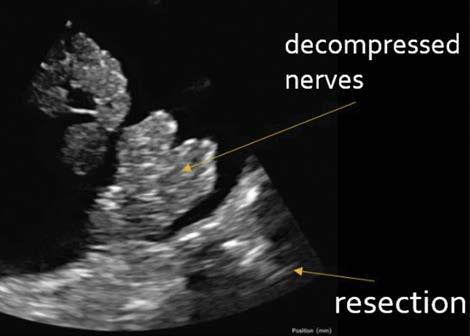

Dal scientists develop device that helps improve spinal surgery outcomes

It’s estimated that 80 per cent of people will experience back pain, with up to 20 per cent of those undergoing surgery at some point to relieve the nagging discomfort.

Many of those procedures are done with a minimally invasive approach rather than open surgery, thereby reducing both the time to perform surgery and the trauma experienced by the patient. Sometimes, however, the area of the spinal cord or nerve root compression can be obscured by body parts, which can result in ongoing symptoms or the need for further surgery.

Dalhousie researchers think they can change that by giving surgeons “eyes” on the injury.

They have developed a sleek, high-resolution probe that can travel to the site of the spinal compression and provide a clear view of the surgical area before and after the procedure is done to make sure the nerve has been decompressed.

The result? A significant reduction in the number of surgeries that have to be repeated.

“It goes right next to the spinal cord in the surgical pathway,” says Dr. Jeremy Brown, a professor in Dalhousie’s School of Biomedical Engineering, who developed the endoscopic imaging probe. “So, you can take some images before the surgeon removes the herniated disc or whatever is compressing the spinal cord, the surgeon then removes the material surgically and then you take some more images and say, ‘OK, is the

nerve still being compressed or is it free now?’”

The probe is guided to the site of the compression through 18-millimetre tubes and can then begin to capture images.

After receiving Research Ethics Board approvals to use the device on 20 patients, Dr. Brown worked with Dalhousie professor and neurosurgeon Dr. Sean Christie to test the probe on an observational basis and validate its efficacy.

So far, Dr. Brown has used the probe on three patients undergoing spinal cord surgeries. The results were remarkable, with the probe providing a vivid view of the spinal anatomy and nerves previously unseen by the surgeon.

“What was surprising was because the resolution is amazingly high, we saw anatomy inside of the sac that goes around spinal cord. We could see nerves and other things that the surgeon said we had never seen before,” says Dr. Brown, adding that this raised the possibility of using the probe in other medical procedures.—Alison Auld

A sleek, high-resolution imaging probe developed at Dal provides a vivid view of spinal anatomy that helps doctors be more precise during surgery.

High-resolution image captured by researchers shows a decompressed nerve.